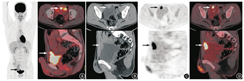

患者男,27岁,3个月前因肉眼血尿在当地医院行膀胱镜检查,于膀胱底部见2.0 cm×2.5 cm乳头状肿物,质脆,触之易出血。随后行经尿道膀胱肿瘤电切术,术后病理示膀胱浸润性腺癌,浸润至固有膜,提示临床关注病灶是原发还是转移性,有否腺癌病史,特别是大肠癌、前列腺癌病史。术后患者继续出现肉眼血尿,入住本院进一步诊治。体格检查无特殊,肿瘤标志物[癌胚抗原(carcinoembryonic antigen, CEA)、甲胎蛋白(alphafetoprotein, AFP)、铁蛋白(ferritin, FERR)、糖类抗原(carbohydrate antigen, CA)125、CA15-3、CA19-9、总前列腺特异抗原(total prostate specific antigen, tPSA)、游离前列腺特异抗原(free prostate specific antigen, fPSA)、fPSA/tPSA、鳞状细胞癌(简称鳞癌)抗原(squamous cell carcinoma antigen, SCCA)、细胞角蛋白19片段(cytokeratin 19 fragment, CYFRA21-1)、CA72-4、神经元特异性烯醇化酶(neuron-specific enolase, NSE)]、肝肾功能电解质全套及大便常规均未见异常。原病理切片会诊意见为:膀胱中等分化腺癌,结合免疫组织化学检查结果,考虑肠道来源可能性大。本院CT泌尿系统成像检查(图1)示膀胱顶前壁实性肿块,突向膀胱外生长,周围组织间隙较清晰,大小为1.2 cm×2.4 cm×3.1 cm,呈明显不均匀强化。为进一步明确病变性质、查找膀胱外可疑原发灶及其他部位转移灶,行18F-脱氧葡萄糖(fluorodeoxyglucose,FDG)PET/CT(德国Siemens mCT-s64型)全身显像。检查前患者禁食6 h、测血糖(5.6 mmol/L),静脉注射18F-FDG 229.4 MBq(患者体质量58 kg),平静休息1 h后显像。嘱患者口服呋塞米20 mg、多饮水、多排尿,以促排膀胱尿液放射性,2 h后行腹盆腔延迟显像(检查前饮水憋尿),影像表现(图2):膀胱顶前壁软组织肿块,18F-FDG摄取异常增高,早期及延迟最大标准摄取值(maximum standardized uptake value, SUVmax)分别为24.8、26.7;双侧盆壁未见明显肿大淋巴结;肠管及全身其他部位未见明显异常18F-FDG高代谢灶。PET/CT显像提示膀胱恶性肿瘤性病变,未见淋巴结及远处转移。随后的肠镜检查未发现明显异常。最终行腹腔镜下膀胱扩大切除术及双侧盆腔淋巴结清扫术,术后病理检查示:膀胱中等分化脐尿管腺癌,肿瘤从膀胱浆膜层浸润至固有层并伴坏死及多核巨细胞反应;双侧盆腔共17枚淋巴结未见癌转移;脐周皮肤未见癌浸润。

脐尿管癌的18F-FDG PET/CT影像学特点:病灶多位于残余脐尿管中下段与膀胱顶部或前壁交界处,与膀胱关系密切,起源于膀胱壁外,由外向内浸润,多以向腔外生长为主;多为单发囊实性肿块,边缘或中心可伴钙化灶,肿瘤囊壁及实性部分多呈轻中度强化;进展期病灶边界多不光整,可侵及膀胱黏膜、邻近腹肌和腹膜等结构,可伴发盆腔淋巴结或远处转移;PET/CT显像病灶实性部分多呈异常FDG高摄取[5,10,11,12]。

尽管脐尿管癌有18F-FDG高摄取特点,但18F-FDG显像对膀胱病灶的显示有一定局限性:18F-FDG从泌尿系统排泄,导致膀胱中的尿液具有较高的放射性,会掩盖膀胱壁病灶的显示;常规显像在排尿后进行,膀胱处于排空状态,膀胱壁较厚,不利于对病变的显示。有研究指出,利尿联合水化后的18F-FDG PET/CT延迟显像不仅能够提高对膀胱病灶的诊断灵敏度和准确性,更有利于对病变进行性质判断[13,14]。一般2~3 h后行延迟显像,显像前嘱患者饮水憋尿,使膀胱处于充盈状态;对于大量饮水有困难的患者,可适当延后其延迟显像时间。